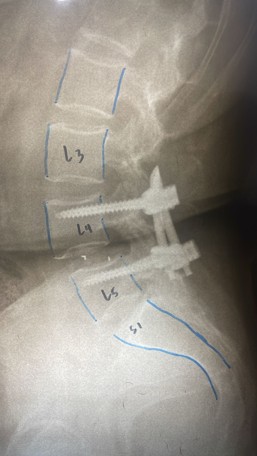

• Estabilización posterior con tornillos: Puede ser necesaria la colocación de tornillos posteriores de forma percutánea (mínimamente invasiva) o abierta. Estos tornillos pueden retirarse una vez que la fractura se considera curada (generalmente entre 8 meses y un año).

fractura de vertebras postquirurgico